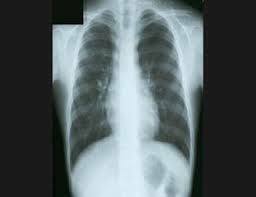

Funda el Instituto del Radio donde se estudiaron las aplicaciones de los Rayos X en medicina.

• Marie Curie